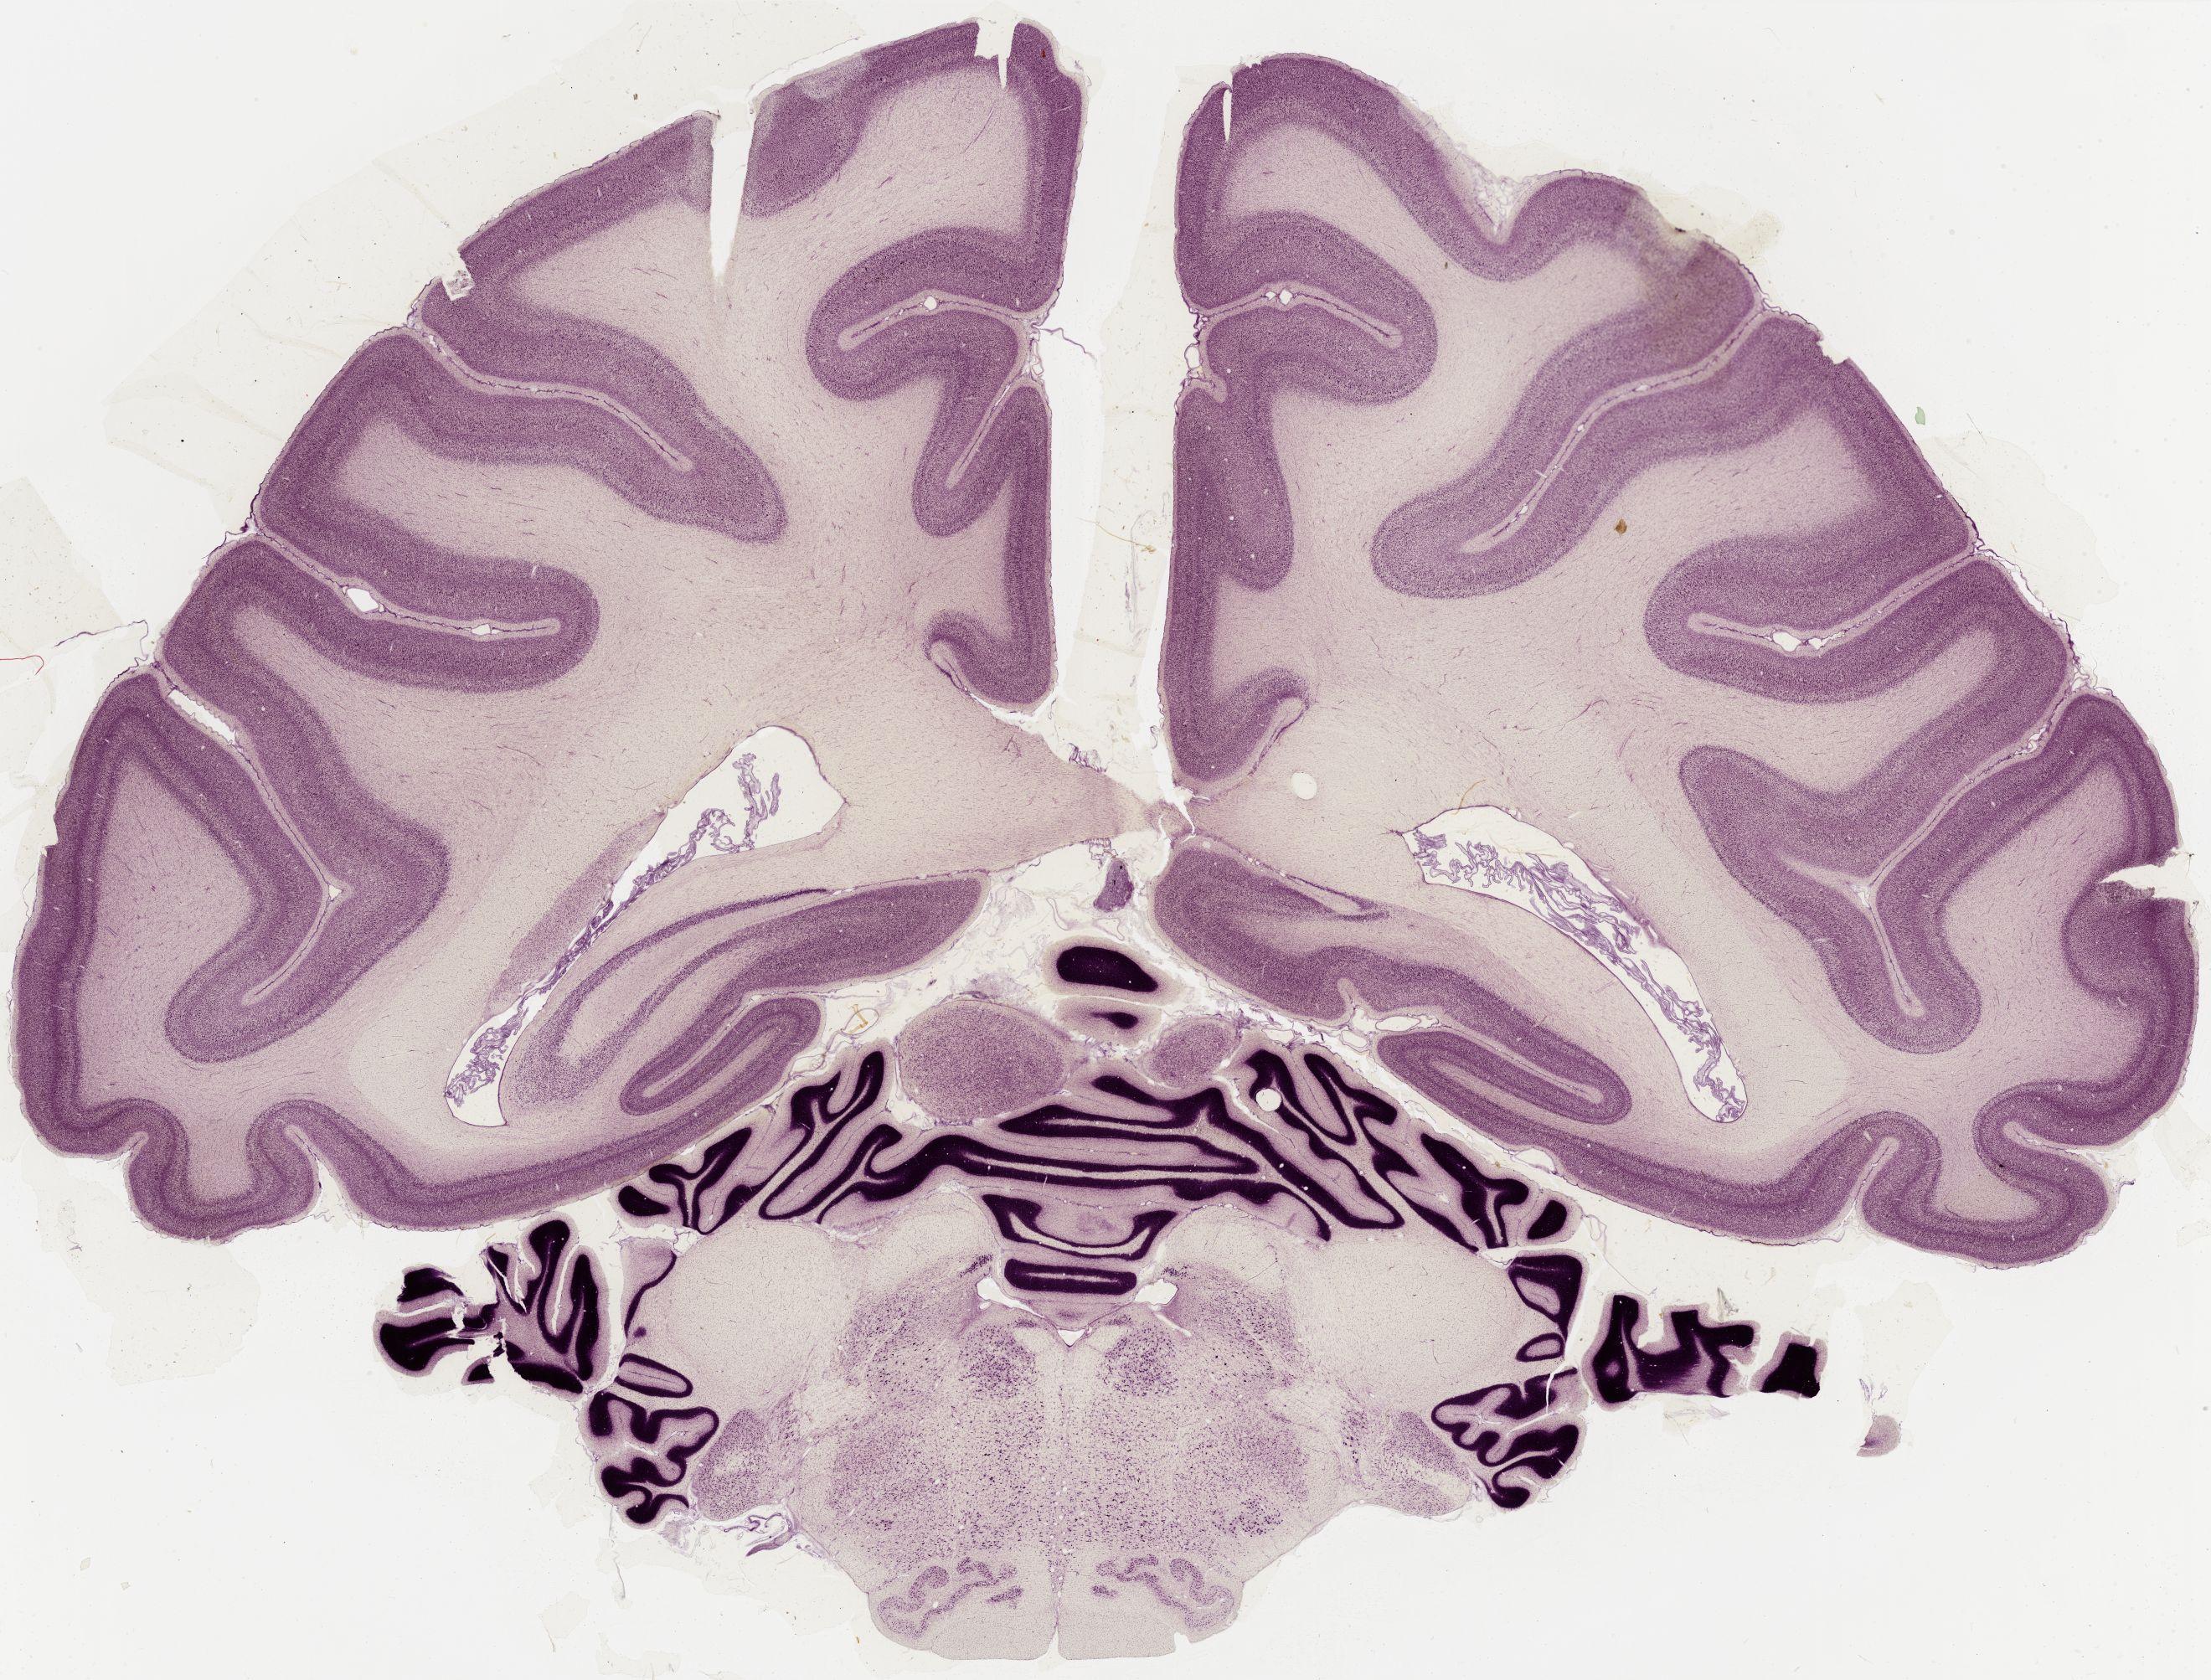

Datasets -> Macaca Mulatta -> Nissl, coronal, histo, Whole-Brain, adult

[ Metadata ]   ·   Source: Edward G. Jones

thumbnail

0650 - labeled